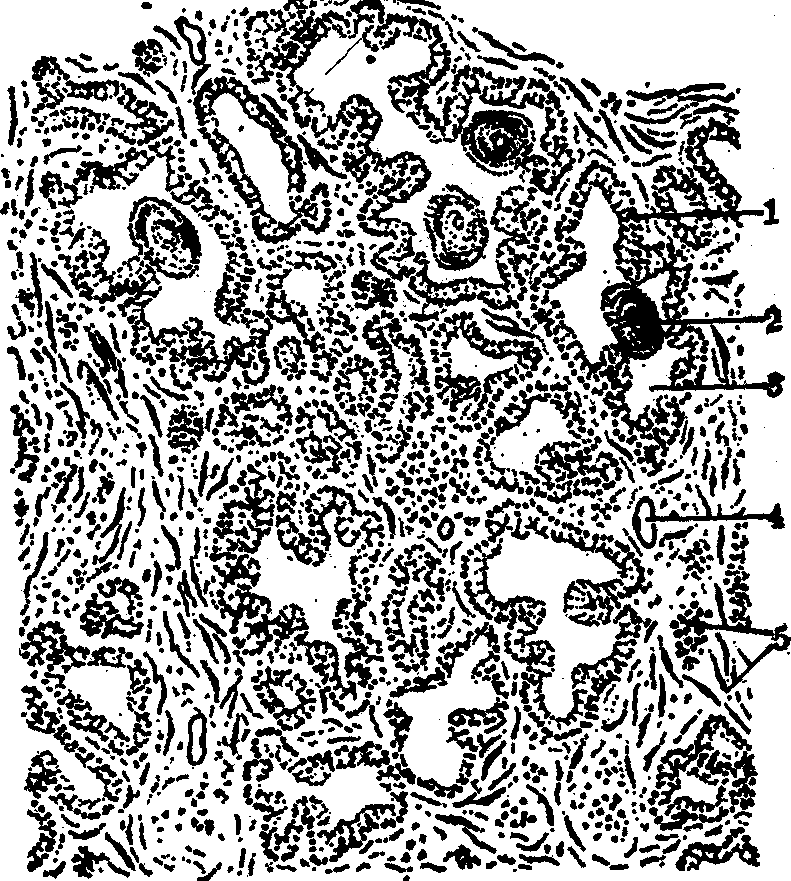

前列腺是男性生殖系统的附属腺,位于膀胱下方,环绕尿道起始段,呈栗子形,由30~50个复管泡状腺组成,汇成15~30条导管,分别开口于尿道。结缔组织和平滑肌构成前列腺被膜,并伸入腺内构成腺的间质,分隔包围腺泡和导管。前列腺的腺泡腔较大,腺上皮常形成许多乳头或皱襞伸入腺腔,故腺腔很不规则。腺上皮类型不一,由单层立方、单层柱状以至假复层柱状,其变化与雄激素的水平有关。腺泡细胞的胞质内有丰富的粗面内质网,核上区有发达的高尔基复合体,顶部含大量分泌颗粒。上皮细胞有较强的酸性磷酸酶活性,腺腔内常有圆形或卵圆形的前列腺凝固体,直径0.2~2mm。凝固体是由分泌物浓缩而成,可发生钙化,其切面呈同心圆的板层状(见图)。这种结构随年龄而增多。

前列腺光镜模式图

1.腺上皮 2.凝固体 3.腺泡腔 4.毛细血管 5.平滑肌